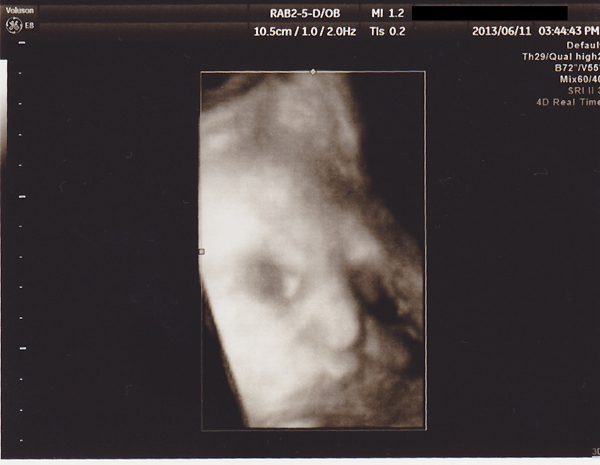

赤子の発育具合は相変わらず2週程度大きめ。

エコー見たら全体的に中の人がデカイので貧血も体重増もそのせいもあると思いたい。